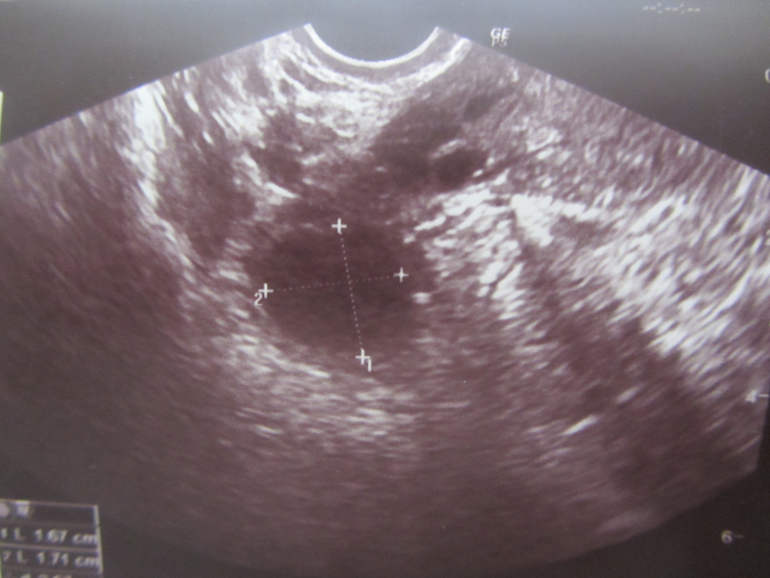

Это мы еще на стадии фолликула :)